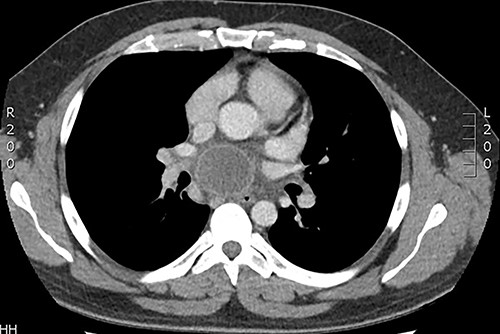

Our first case was a 66-year-gentleman male with an incidental large subcarinal mass identified on contrast enhanced CT scan during pre-operative investigations for an infra-renal abdominal aortic aneurysm. He had previously undergone left thoracotomy and decortication following parapneumonic empyema 20 years ago. Contrast enhanced CT thorax revealed a 6 × 5 × 4-cm subcarinal mass measuring 65-Hounsfield unit and a 6-cm infrarenal aneurysm. He was referred to the respiratory physicians for further investigations of this mediastinal mass. Following discussion at the multidisciplinary meeting (MDT), there were concerns of mediastinal lymphadenopathy and he underwent EBUS, which showed a heterogeneous echogenic lesion in keeping with solid/semi-solid with multiple foci of calcium within it. EBUS guided biopsy revealed gel like material raising concerns of a suspicious mass. The infrarenal aneurysm was to be kept under surveillance. Five days following the procedure the patient presented to hospital in septic shock. Repeat CT imaging demonstrated an enlarged cyst 7.6 × 6.3 × 5.5-cm compressing the right pulmonary artery with a tense pericardium and pleural effusion (Fig. 1). The patient was haemodynamically unstable with cardiac tamponade and was admitted to intensive care for inotropic support and stabilisation prior to undergoing emergency surgery. Right posterolateral thoracotomy was performed, which revealed pyopericardium and purulent material with dense adhesions in the subcarinal region and its surrounding structures. The pericardium was opened, and the cavity irrigated with saline. The cyst was completely de-roofed and excised as much as possible. Copious washout was performed, and multiple drains were inserted. The patient returned in a stable condition to intensive care where he progressed satisfactorily and later recovered on the eventually discharged following completion of intravenous antibiotic therapy 21 days after admission. Histology demonstrated appearances consistent with infected bronchogenic cyst. Microbiology demonstrated pus cells with no growth on culture.

Axial CT demonstrating large subcarinal mass and pericardial effusion.